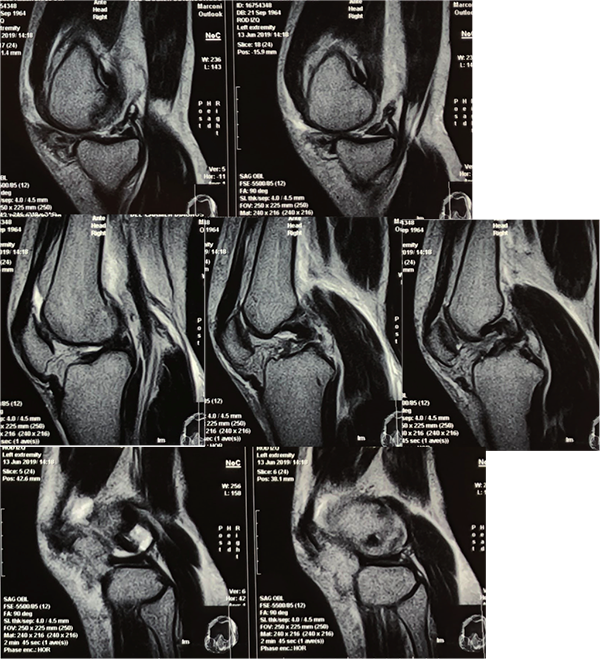

Figura 1: RM de rodilla izquierda. Secuencia T2 y T1 en cortes coronales. Se observa lesión completa del ligamento colateral interno con compromiso de componente menisco femoral (hoja profunda) al momento del trauma.

Figura 2: RM cortes sagitales secuencia T1. Se observa la traslación posterior de la tibia. Tendón rotuliano laxo como signo de inestabilidad posterior. Lesión grado III del cuerno posterior del menisco interno, trazo oblicuo asociado a luxación de la tibia. Lesión completa de ambos ligamentos cruzados (LCA – LCP). Menisco externo sin lesión objetiva.